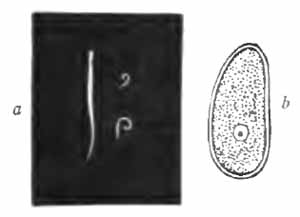

Crystals of nitrate of urea and oxalate of urea

FIG. 19.—Crystals of nitrate of urea (upper half) and oxalate of urea (lower half) (after Funke).

The presence of urea can be shown by allowing a few drops of the fluid to partially evaporate upon a slide, and adding a small drop of pure colorless nitric acid or saturated solution of oxalic acid. Crystals of urea nitrate or oxalate (Fig. 19) will soon appear and can be recognized with the microscope.